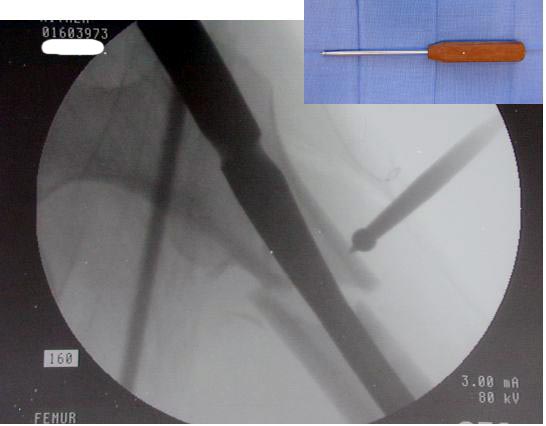

Большие преимущества у интрамедуллярных штифтов, метод хорош и можно произвести из минимального доступа, но во время операции необходимо контролирование варуса, затем приступить к блокированию.

слайды:

Long TFN

Short TFN

IMHS

DePuy Trochanteric Nail

Контролировать варус